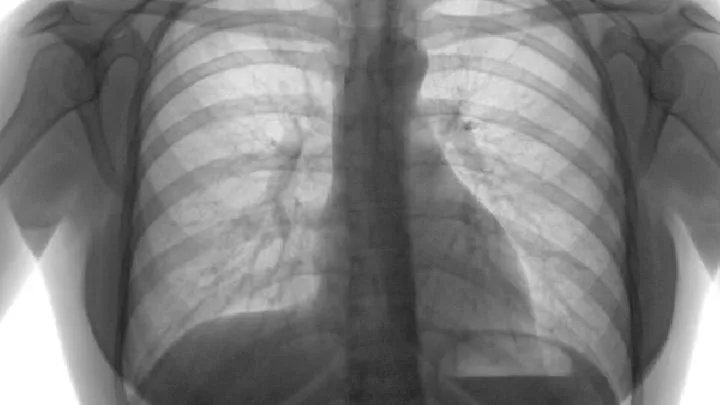

2.研究表明,肺癌不具有传染性,但其遗传性不容忽视。临床调查显示,在肺癌患者中,血缘关系患者的发病率远高于无血缘关系患者,近亲患者的发病率也高于远亲患者。为了有效预防肺癌的发生,如果人们有肺癌家族史,需要及时定期检查,并采取相关保护措施,以实现早期发现和早期治疗。